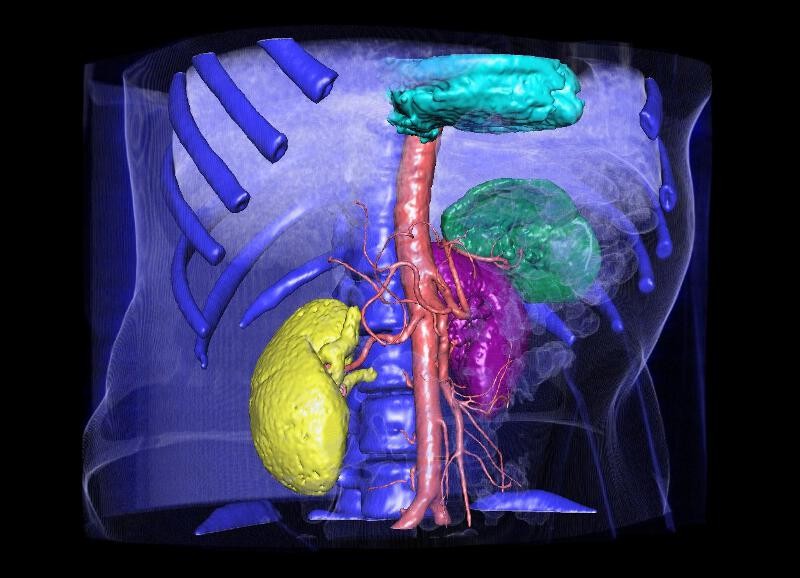

Karl-Ingo Friese studierte Mathematik mit Studienrichtung Informatik an der Universität Hannover und schrieb seine Diplomarbeit zum Thema "Randflächenrekonstruktion von Volumenkörpern anhand diskreter Daten". 2002 beendete er sein Studium und arbeitet seitdem als Wissenschaftlicher Mitarbeiter am Lehrstuhl für Graphische Datenverarbeitung, Institut für Mensch - Maschine - Kommunikation der Leibniz Universität Hannover. Dort schrieb er auch seine Promotion mit dem Thema "Entwicklung einer Plattform zur 3D-Visualisierung und -Segmentierung medizinischer Daten" (YaDiV).

Mein Forschungsschwerpunkt liegt im Bereich der Visualisierung, konkret der Visualisierung medizinischer Daten. Zur Zeit arbeite ich an einer umfangreichen Visualisierungs- und Segmentierungssoftware fĂĽr DICOM Dateien, die auch Gegenstand meiner Promotion war.

Einige zufällig ausgewählte Bilder aus meiner Forschung:

kif_research

research pictures on ingos homepage